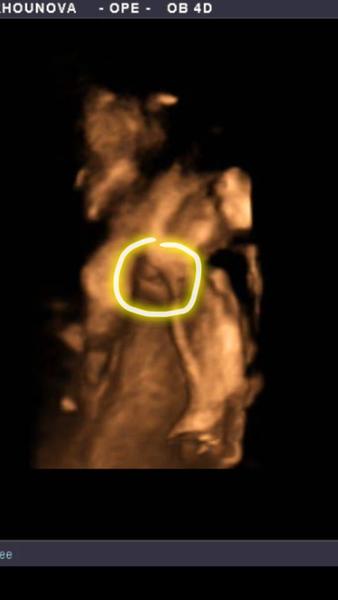

@anonym1987 bohužel nevidim nic krome nozicky muzes dat pohlaví do krouzku?

@anonym1987